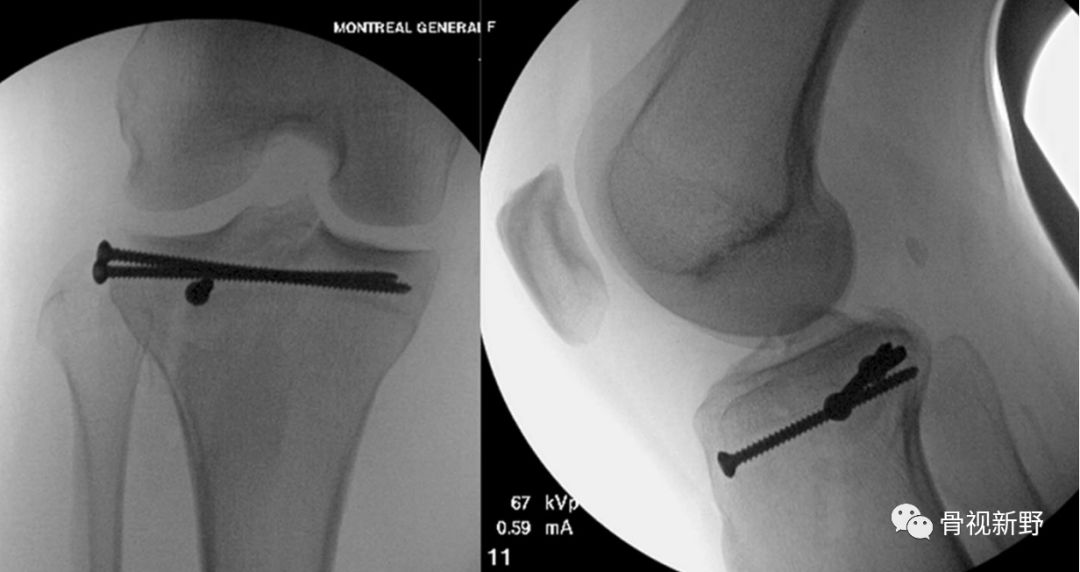

Moran E(2017)对传统“三角螺钉固定”技术进行改良,将第3枚防滑螺钉的方向朝向拉力螺钉的尖端而形成螺钉尖端汇聚,螺钉分布在侧位呈倒“品”字形进钉;正位X光片(或透视)像上螺钉呈三角形分布(如下图)。

具体固定方法:2枚带垫片、相互平行的6.5 mm半螺纹拉力螺钉(相距15 mm)垂直骨折线在距关节面7mm以下打入软骨下骨。第3枚三角固定螺钉选择带垫片的全螺纹6.5mm 松质骨螺钉,从骨折块尖端呈30°角(正位透视)打入,螺钉尖部与2枚拉力螺钉尖部汇合,第3枚螺钉起防滑、支持作用( Moran E 2017)。